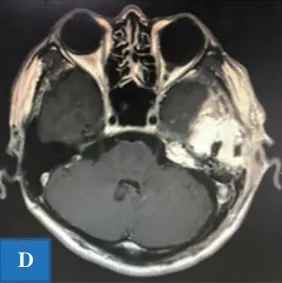

A&B:术前轴向和冠状面计算机断层扫描图像,显示岩骨水平的内听道。一个巨大的高颈静脉球延伸到后颅窝;

C&D:术后图像显示切除的内耳道前壁和上壁。